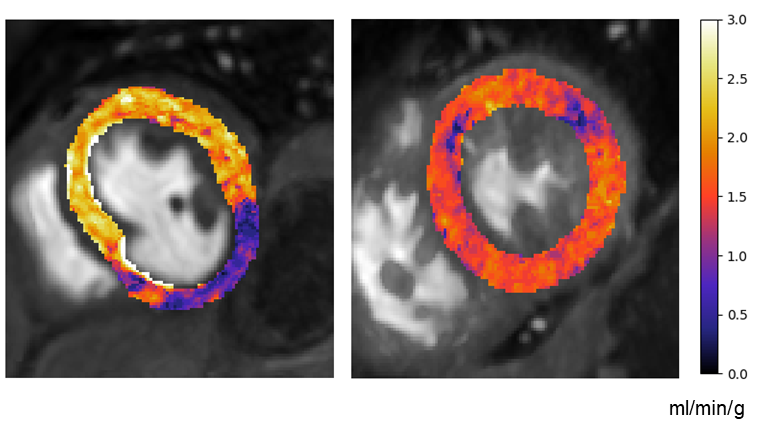

Since this, deep learning has been widely adopted in the field of medical imaging and has become the de facto standard for many processing tasks Litjens2017. Trends in cardiac MRI image analysis have followed a similar route where deep learning is now used for everything from reconstruction to detection and segmentation tasks to automating diagnostics and prognostics Leiner2019.

The main advantage of deep learning is that the networks learn the features to be used to complete the task from the data rather than these being hand-engineered. Such hand-crafted features are biased by preconceived ideas of the programmer and thus tend to be brittle. An example of this, in the context of perfusion CMR, is the problem of bounding box detection which is a common first step in processing pipelines. Before the advent of deep learning, a popular approach for this task was based on thresholding temporal variances. The logic behind this was that the contrast flowing causes the areas of highest temporal variance to be the RV and LV cavity. However, this approach was shown to fail in 4/44 case Tautz2011a and we found similarly high rates of failure in our implementation. An example of this algorithm with some of the common failure modes is shown in Figure 5.1. For this reason, deep learning is used in this work for the image processing required to turn the raw image series into concentration curves for tracer-kinetic modelling.

Refer to caption

Fig. 5.1: The top row shows the temporal standard deviation image, the thresholded standard deviations, and the result of the connected component analysis to identify the RV and LV (from left to right). The bottom row shows two failed cases. On the left, there only one component (a joint LV and RV) is identified and on the right four similar components are identified.

5.1.1 Supervised deep learning for image processing

Supervised learning

Supervised learning attempts to learn a model that takes input data and outputs labels Goodfellow2016. That is, to learn the function f𝑓f which depends on parameters 𝜽𝜽\boldsymbol{\theta} that best maps the input space X𝑋\mathit{X} to the output space Y𝑌\mathit{Y}:

f𝜽:XY.:subscript𝑓𝜽𝑋𝑌\displaystyle f_{\boldsymbol{\theta}}:\mathit{X}\rightarrow\mathit{Y}. (5.1)